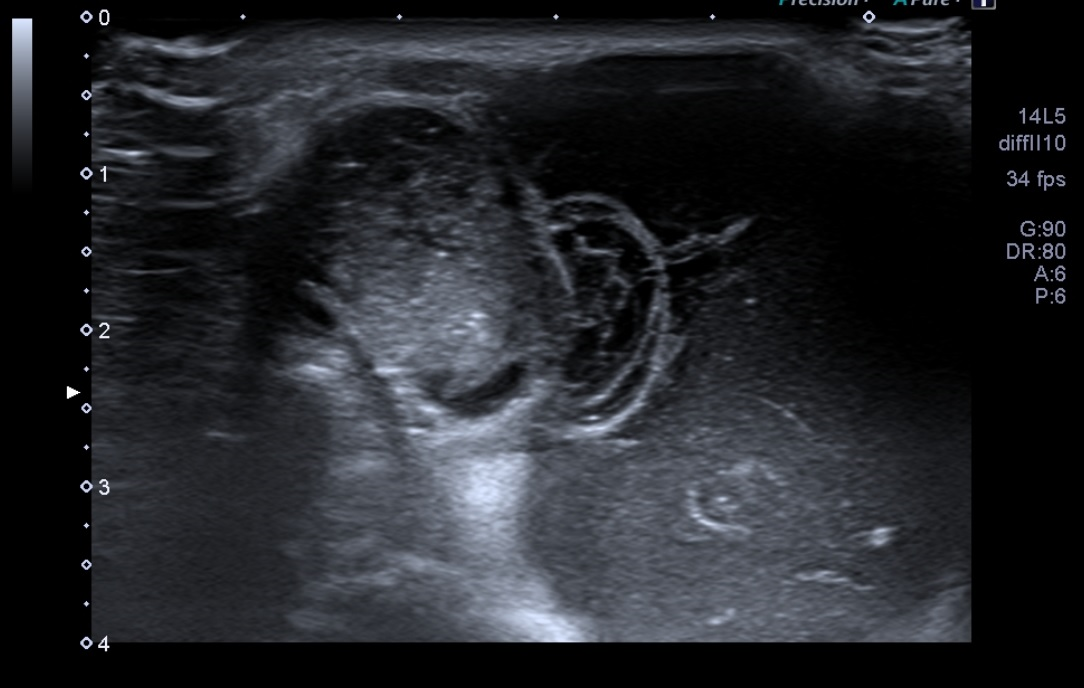

Ecografía de Radiología: La masa que se palpa en el hombro izquierdo se corresponde con una masa quística que nace desde la articulación acromionclavicular en relación con rotura del manguito de los rotadores identificándose compromiso del supra e infraespinoso.